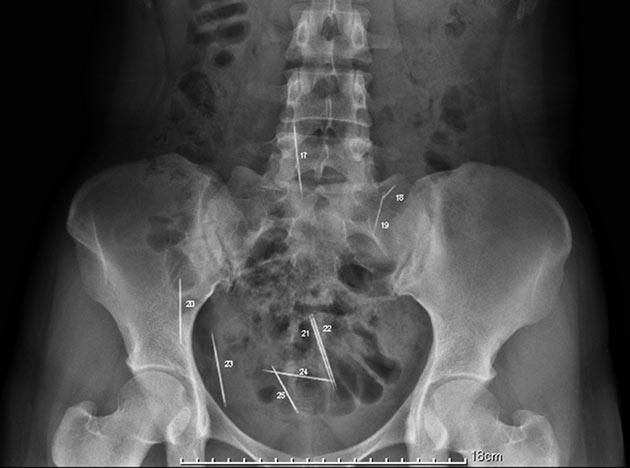

Foto del 13 de febrero de 2011 en Lyon, Francia, que muestra un par de pinzas quirúrgicas en el abdomen Anne, una mujer que se quejó de dolores tras seis meses de haber recibido una cirugía.